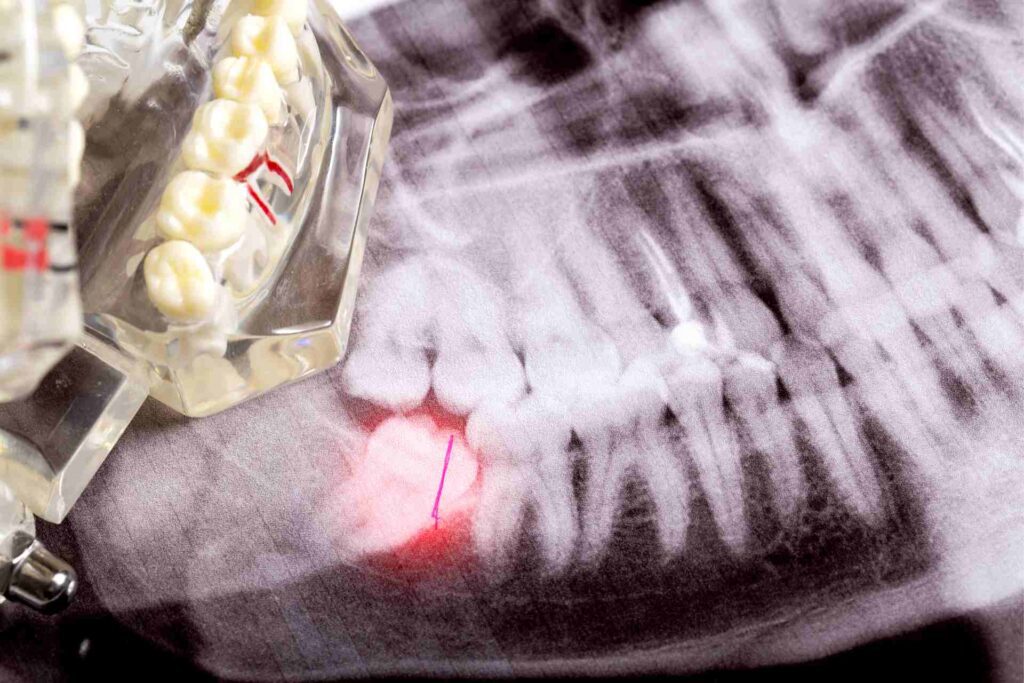

In dental terms, a dry socket, or alveolar osteitis, is a complication that can emerge after a tooth extraction procedure. It’s a painful condition that happens when the blood clot, which serves as a protective layer over the underlying bone and nerve endings, gets dislodged or dissolves.

You’re left with an open area, a ‘dry socket,’ exposing your jawbone and nerves. Trust me, it’s uncomfortable!